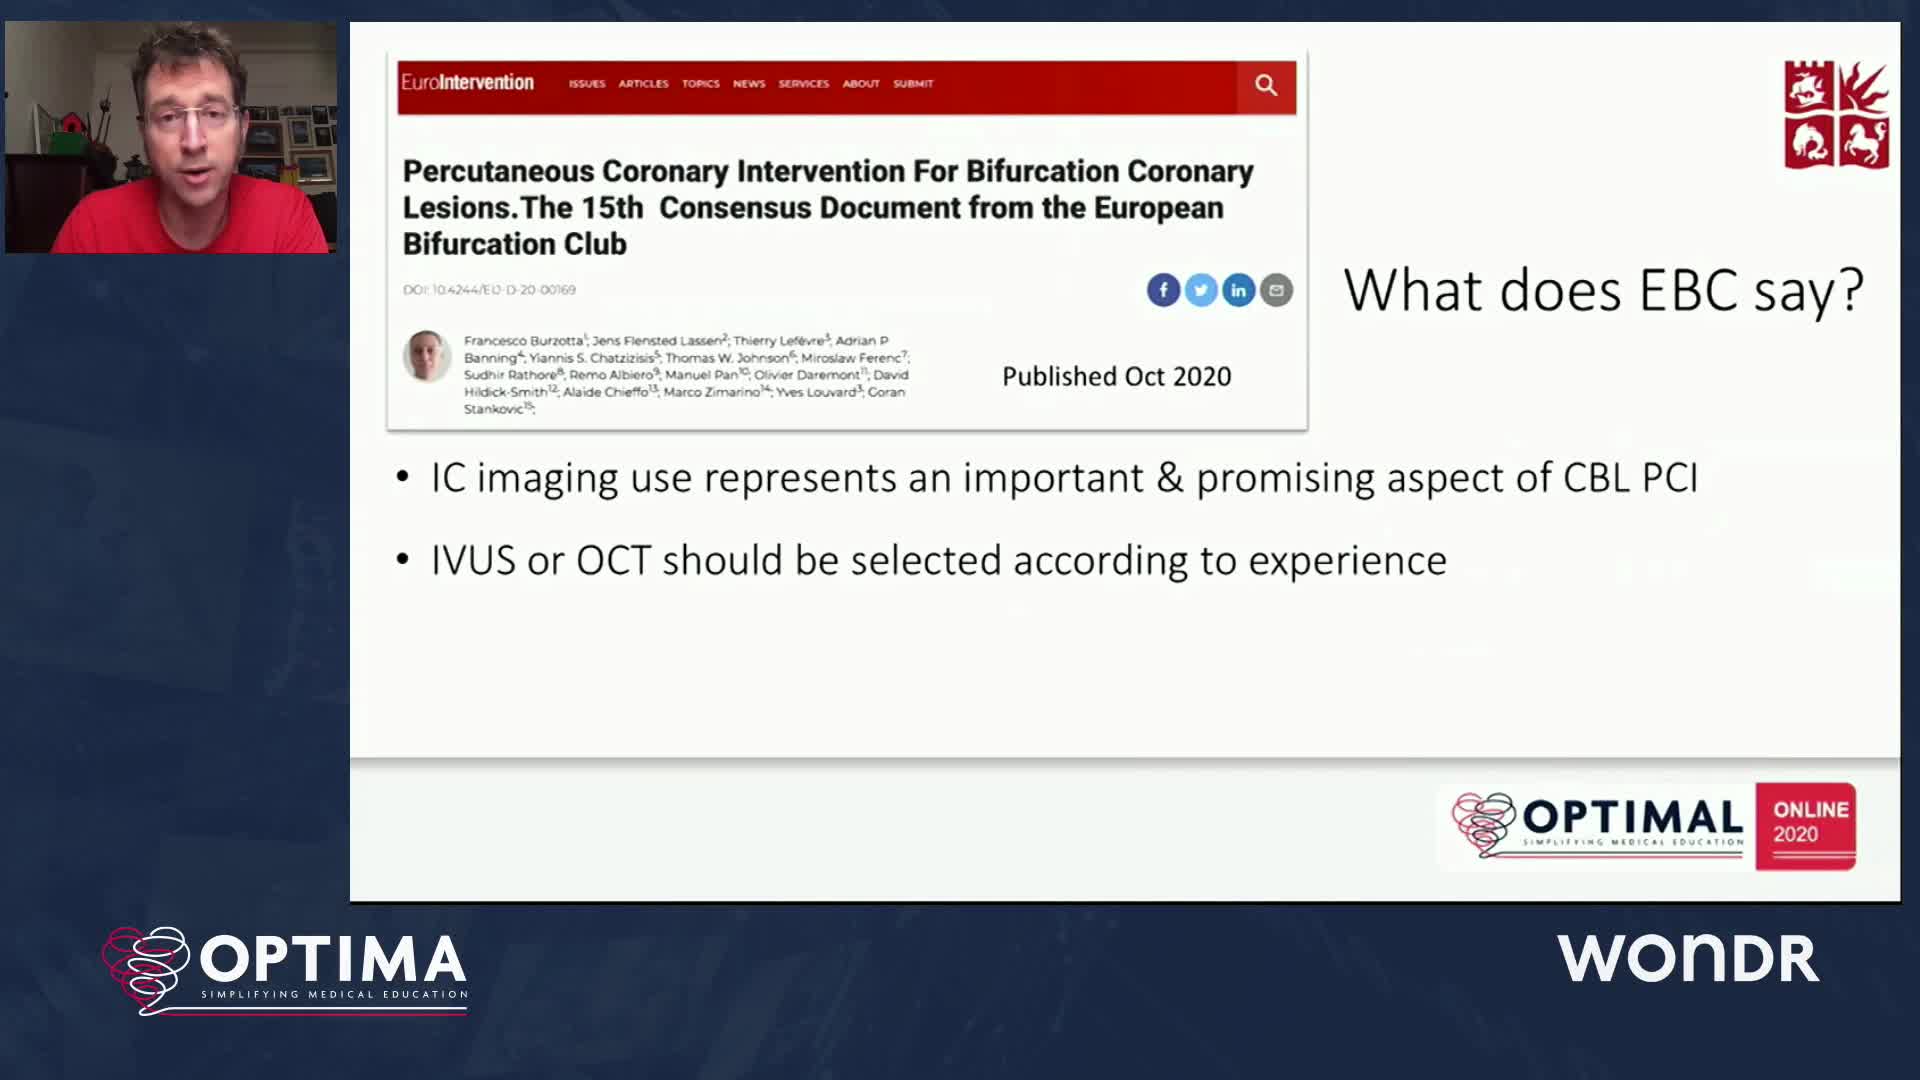

The integrated use of physiology and imaging is transforming the treatment of complex bifurcation disease. We explore...